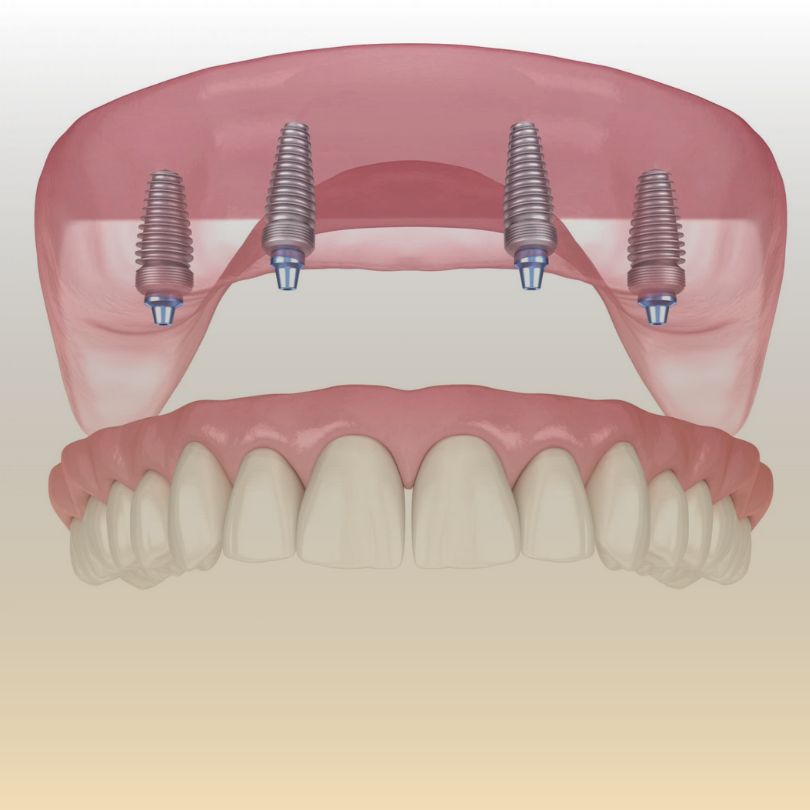

All-on-4®

This innovative technique allows for the replacement of an entire arch of teeth using just four implants, offering a stable and efficient restoration.